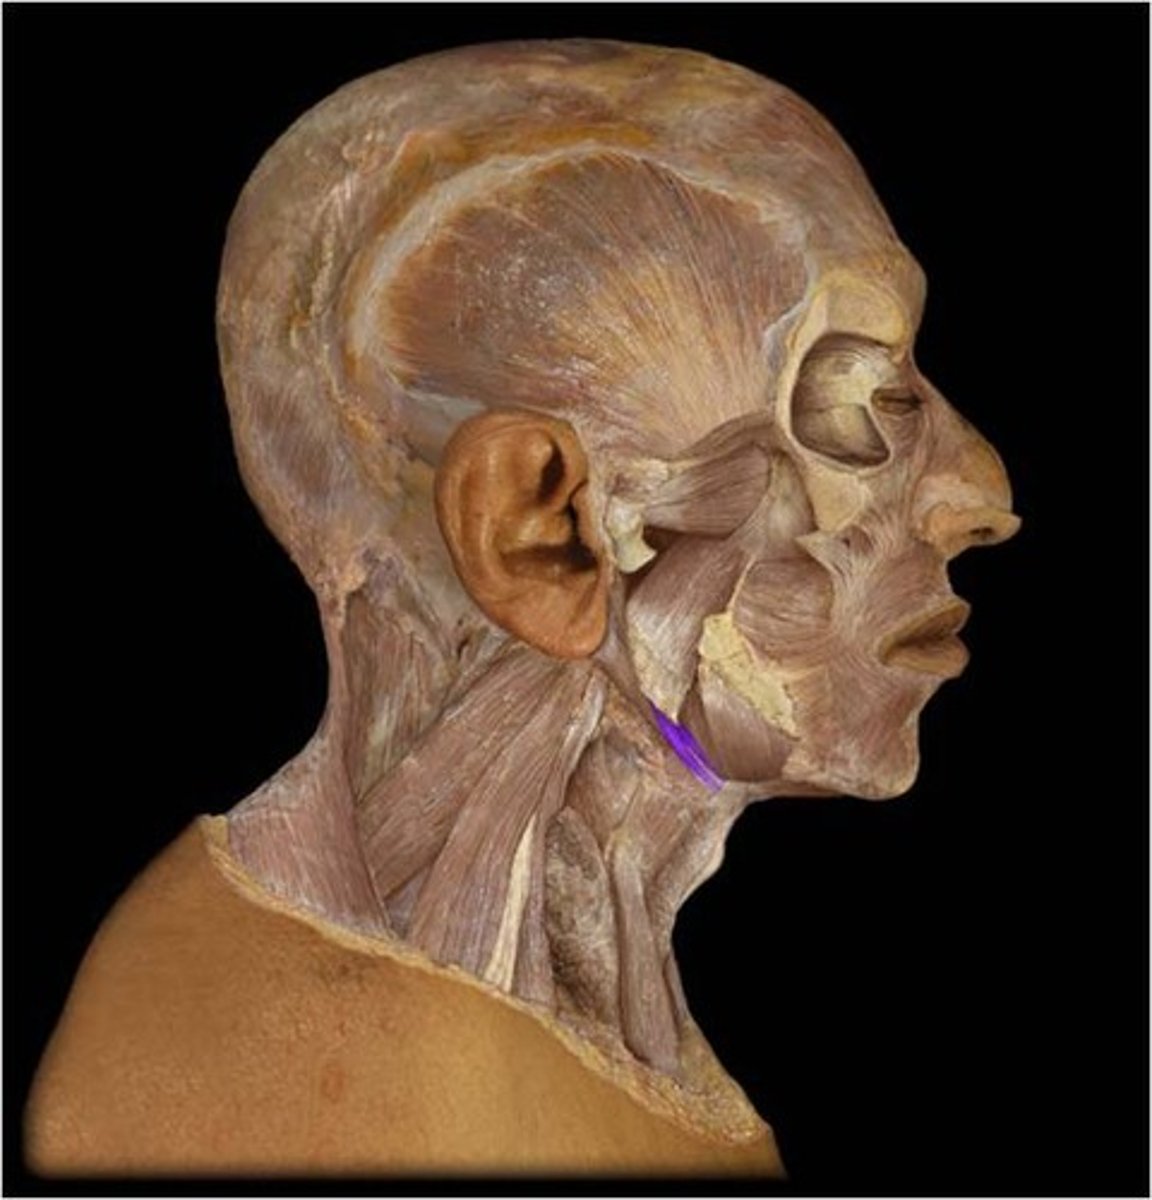

Platysma

Origin: Fascia of deltoid and pectoralis major

Insertion: Mandible, skin and subcutaenous tissue of lower face

Action: depresses mandible, draws angle of mouth downward (pout), tightens skin of the neck

Digastric

Origin: Anterior Belly: Diagastric fossa of mandible: mastoid process of temporal bone

Insertion: Hyoid one via fascial sling

Action: depresses mandible, opens the mouth (when hyoid bone is fixed)